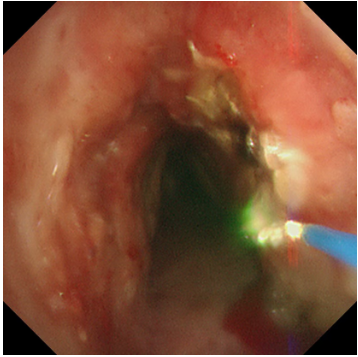

兩種技術(shù)優(yōu)勢互補,相得益彰,在微小創(chuàng)傷的前提下,實現(xiàn)了對復(fù)雜氣道狹窄的最大化疏通。

精準(zhǔn)介入破難題!

此例高難度氣道狹窄激光聯(lián)合冷凍治療的成功,充分體現(xiàn)了我院呼吸內(nèi)科團隊在處理復(fù)雜氣道疾病方面“精準(zhǔn)化、微創(chuàng)化、多學(xué)科一體化”的重大突破。王劍主任指出:對于喉癌術(shù)后、氣管插管或切開后遺留的氣道狹窄,介入肺臟病學(xué)技術(shù)提供了全新的微創(chuàng)解決思路。激光與冷凍的聯(lián)合應(yīng)用,既能快速解除危急,又能追求長期療效,為廣大慢性氣道疾病患者提供了更安全、高效的診療選擇。未來,我院呼吸內(nèi)科將緊跟新近技術(shù)發(fā)展,持續(xù)提升專業(yè)內(nèi)涵,為呼吸系統(tǒng)疾病患者個性化治療方案提供更多選擇,幫助患者改善癥狀,促進康復(fù),提高生活質(zhì)量。